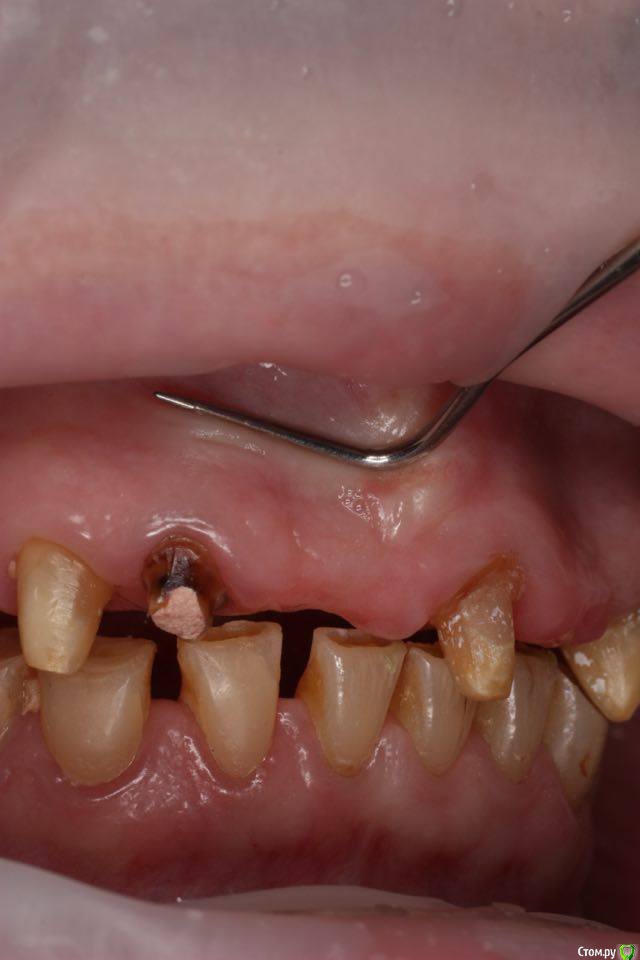

togrul Опубликовано 4 мая, 2016 Поделиться Опубликовано 4 мая, 2016 Добрый день необходим совет по планированию. Планируем удалить зуб 1.2 + одномоментно имплантат Импро 3.6 + ССТ. в области 11 зуба имплантат 3.6 + ССт. у пациента сахарный диабет в районе 8.И 2 вариант НТР в области 11 + имплантация отсрочено. хочу услышать мнение более опытных коллег. буду благодарен. Ссылка на комментарий

togrul Опубликовано 4 мая, 2016 Автор Поделиться Опубликовано 4 мая, 2016 Установить 2 имплантата 1.1 и 1.2 + одиночные коронки. Ссылка на комментарий

togrul Опубликовано 4 мая, 2016 Автор Поделиться Опубликовано 4 мая, 2016 В остальных позициях будут установлены мосты на зубах из финансов. Ссылка на комментарий